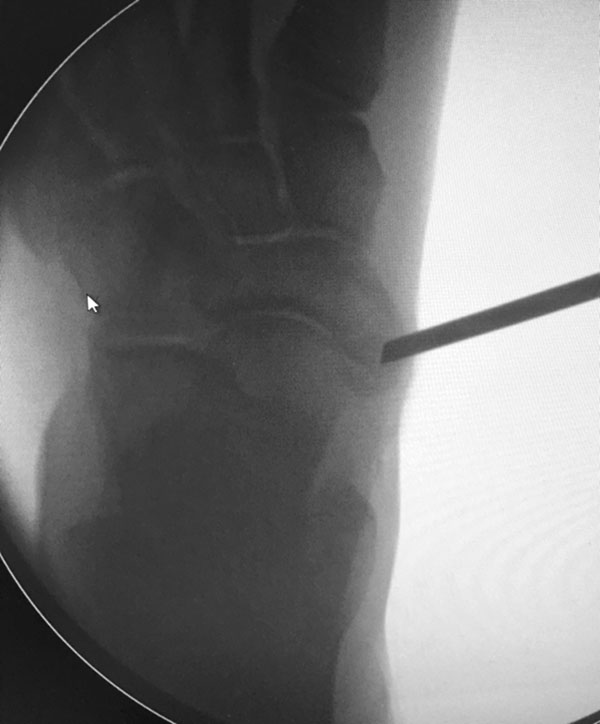

- Intraoperativ iatrogene Osteotomie des Os naviculare außerhalb des Synchondrosen-Spaltes bei Mobilisation des Os tibiale externum. Hier ist die exakte Lage des Synchondrose-Spaltes unter Bildverstärker zu finden und zu dokumentieren, bevor der Spalt mit Meißel mobilisiert wird.

- Fehllage des Knochenankers. Die korrekte Platzierung des Knochenankers wird unter Bildverstärker in 2 Ebenen kontrolliert und dokumentiert.